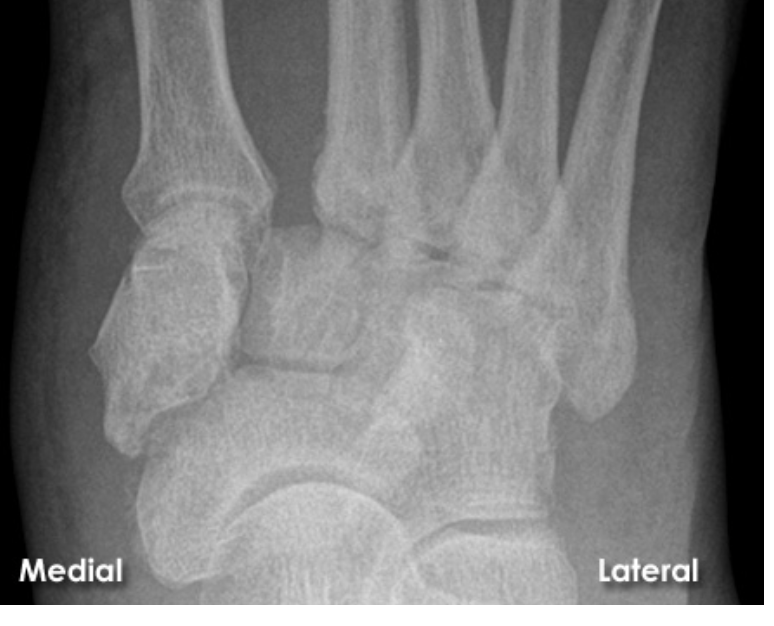

A

A Lisfranc injury is a tarsometatarsal fracture dislocation characterized by traumatic disruption between the articulation of the medial cuneiform and base of the second metatarsal.

* Diagnosis is confirmed by radiographs which may show widening of the interval between the 1st and 2nd ray.

**Lisfranc Injury**